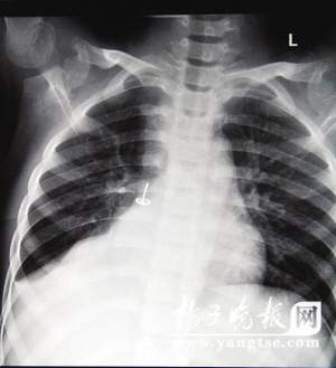

從片子上,圖釘在孩子右肺里“潛伏”得很深,卡在右下葉支氣管。南京市兒童醫(yī)院耳鼻喉科周艾醫(yī)生表示,由于圖釘堵住了孩子支氣管的通道,導(dǎo)致右肺葉不擴(kuò)張,肺部已經(jīng)發(fā)生了實(shí)質(zhì)性的改變,用擴(kuò)張來進(jìn)行氧氣交換的肺泡都已經(jīng)“癟”下去了,所以孩子的肺部功能非常弱。從片子上看,孩子的右肺已經(jīng)嚴(yán)重“萎縮”,比左肺小了一大圈。